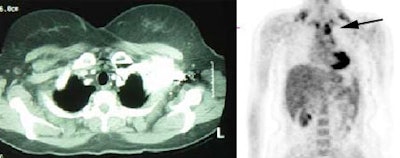

Metastatic melanoma: The patient shown below had a history of a lower extremity melanoma. CT imaging performed as part of the patient's evaluation revealed no evidence of metastatic disease. A FDG PET study demonstrated the presence of multiple lymph node metastases involving the supraclavicular and mediastinal nodes (black arrow). Beam hardening artifact from the I.V. contrast bolus obscured adequate evaluation of these regions on CT. PET imaging provides an excellent whole body survey and is a very sensitive exam for detecting melanoma metastases. Case courtesy of CTI PET Systems, Inc. |